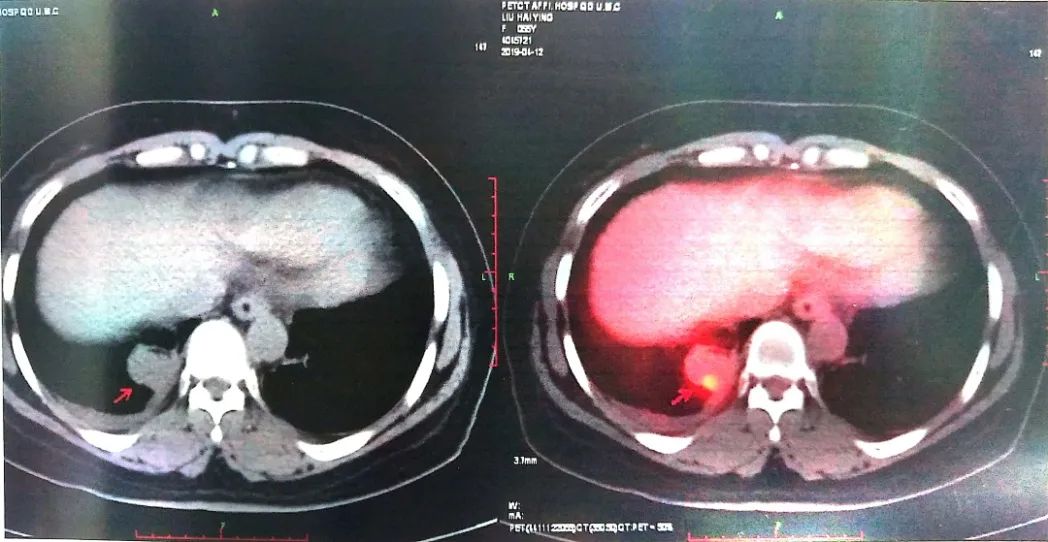

2019-04-12 PET-CT显示①右肺下叶后基底段胸膜下软组织密度肿块(大小26*30mm)。

②左肺下叶纵隔旁软组织密度肿块(大小28*31mm)。

③双肺门、纵隔内隆突下、气管旁、主肺动脉窗、血管前间隙、右侧颈部Ⅴ区及锁骨区多发增大淋巴结。

至此为止,患者的诊断为:肺恶性肿瘤 小细胞癌 广泛期 cT4N3M0 IIIC期(病灶1:右肺下叶,病灶2:左肺下叶),此时先给予标准化疗方案,EP方案:依托泊苷100mg/㎡ d1-3+顺铂75mg/㎡ d1-2 q21d*2。结果如下: